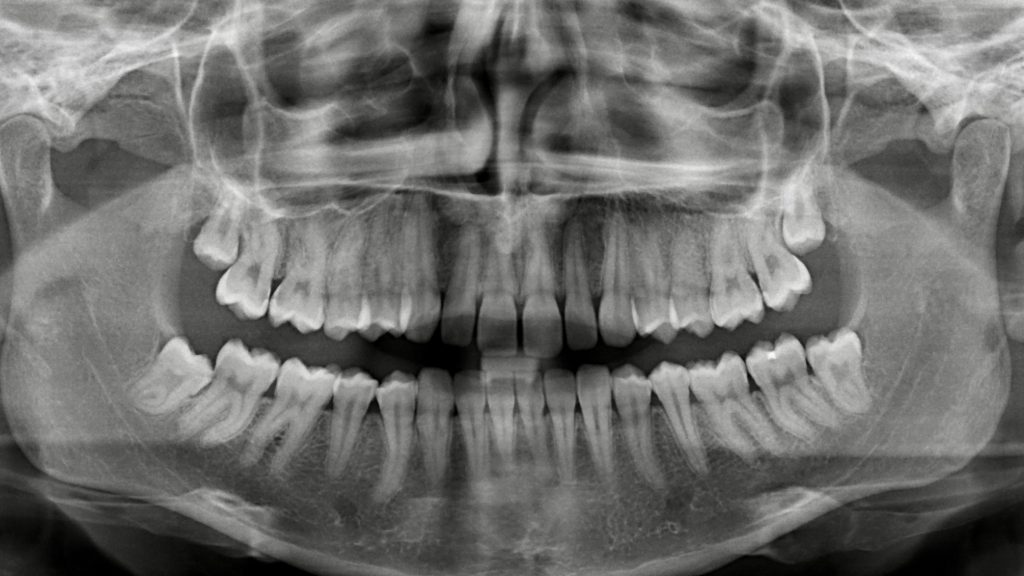

Digitales Röntgen Eine der wichtigsten Untersuchungsmethoden des Zahnarztes ist schon seit Jahrzehnten das Röntgen. Das entstehende Röntgenbild zeigt die innere Beschaffenheit der Zähnen und der Kiefer. Es hilft somit … weiterlesen